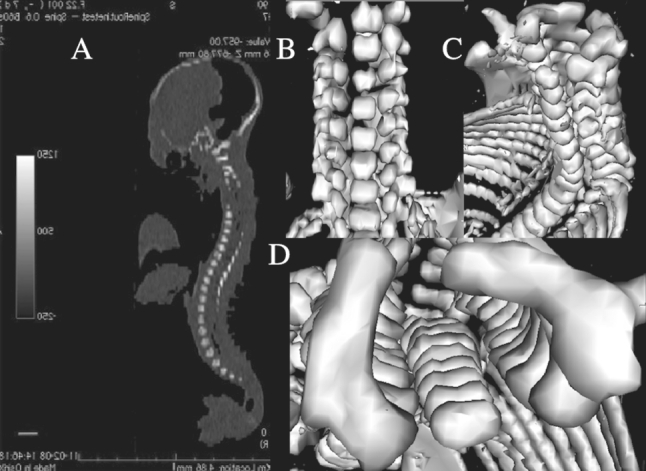

Fig. 1.

CT of a female fetus aged 25 weeks recorded in DICOM formats (a) and assessed by Osirix 3.9 in frontal (b), lateral (c), and horizontal (d) planes

The present study included 55 ethnically homogenous human fetuses (27 males, 28 females) aged 17–30 weeks, of Caucasian racial origin (Table 1), which had been derived from spontaneous abortions or stillbirths in the years 1989–2001 because of placental insufficiency. Gestational ages were determined from measurements of the fetal crown–rump length [14]. No attempt was done to encourage fetal donation. The use of the fetuses for research was accepted by the University Research Ethics Committee (KB 275/2011). None of the fetuses demonstrated visible malformations. For preservation, all specimens were immersed in 10 % neutral buffered formalin solution. The fetuses underwent CT examinations with the reconstructed slice width option of 0.4 mm and 128 slices were acquired simultaneously by Biograph mCT (Siemens). The CT scans obtained were recorded in DICOM formats (Fig. 1a), with possibility to create three-dimensional reconstructions and the morphometric analysis of structures examined. Measurements of the vertebral column could be performed only after identifying vertebra C4. Next, DICOM formats were assessed using digital image analysis of Osirix 3.9 (Fig. 1b–d) with estimating linear (sagittal and transverse diameters, height, length, width), two-dimensional (cross-sectional area), and three-dimensional (volume) parameters of vertebra C4. The contouring procedure of each C4 vertebral body and the three ossification centers was outlined with a cursor and recorded.